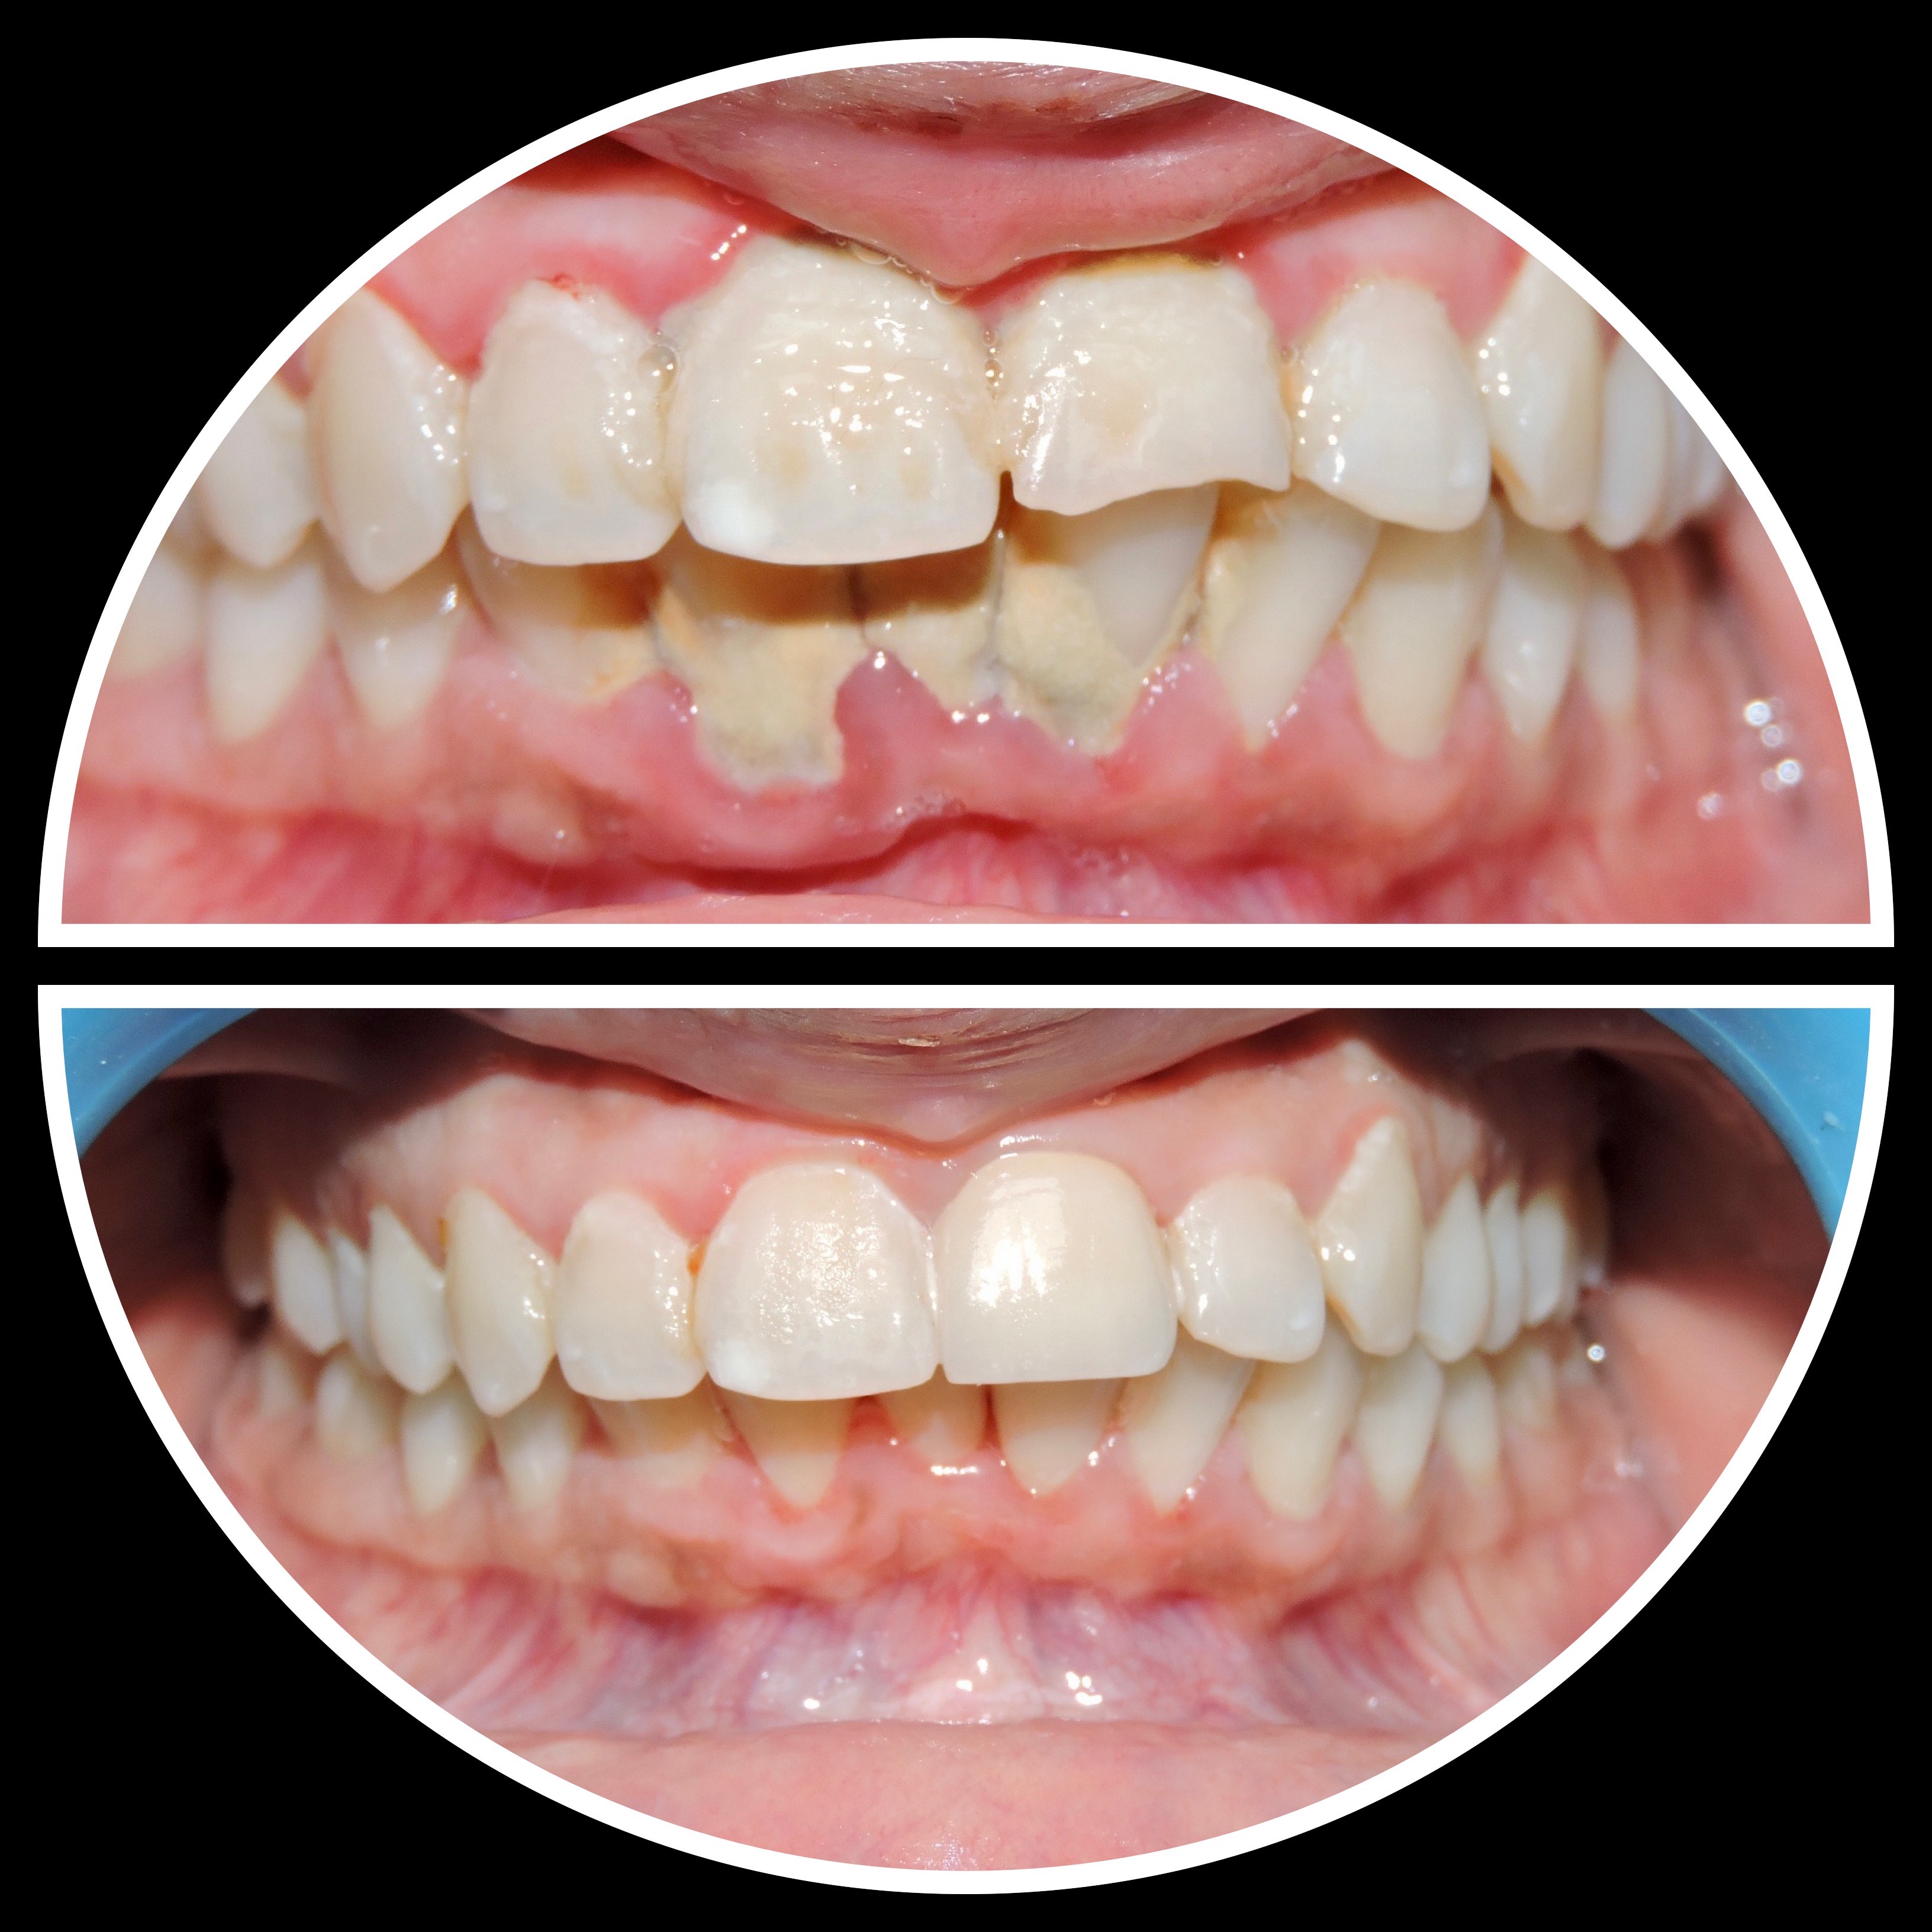

Gallery